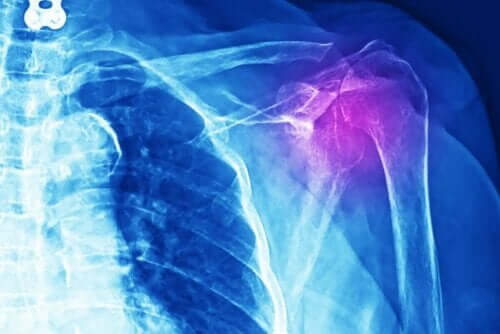

Legene må gjøre forskjellige tester for å diagnostisere denne typen skade. Det kan være røntgen, ultralyd, MR eller datastyrt aksial tomografi (CT-skanning). I tillegg må de gjøre en medisinsk undersøkelse og en detaljert studie av pasientens sykehistorie.